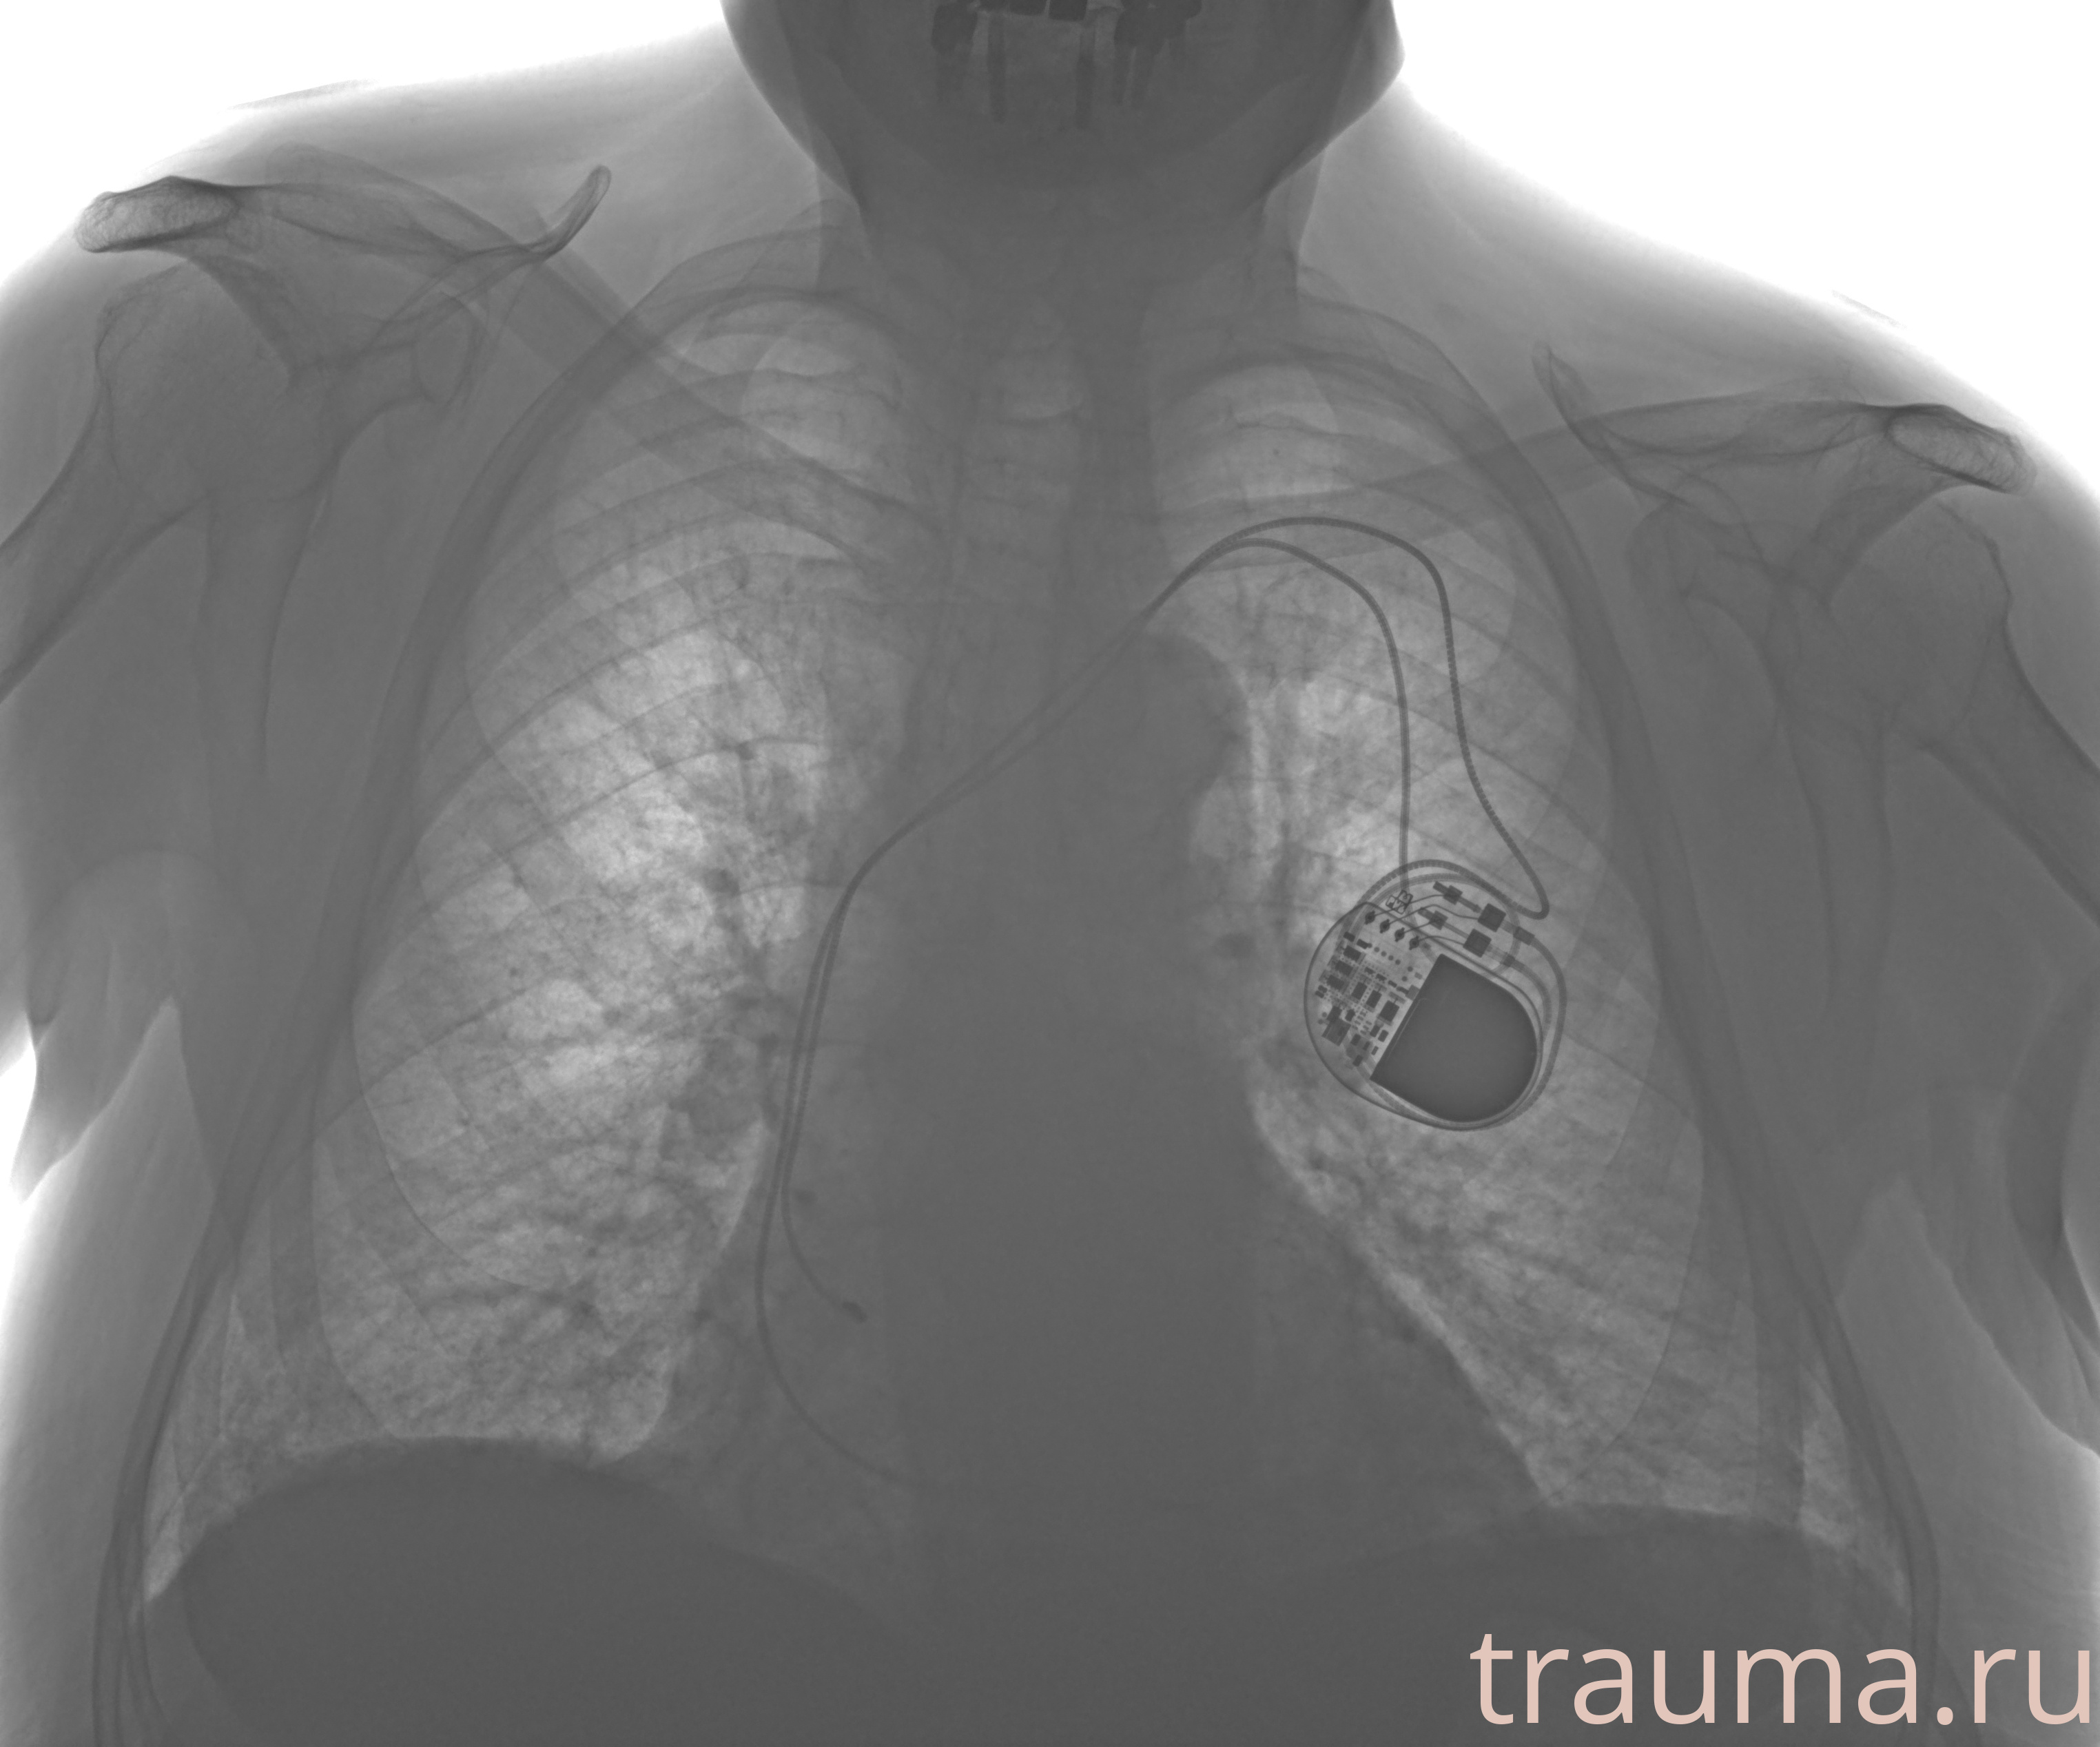

Рентген на дому: по вашему адресу приезжает врач-рентгенолог, травматолог-ортопед с мобильным рентгеновским аппаратом, проводит диагностику травмы или заболевания, делает необходимые рентгенограммы, дает рекомендации по дальнейшему лечению. Получить качественные снимки в домашних условиях возможно благодаря уникальной методике, разработанной МосРентген Центром для института  Склифосовского

при переломе шейки бедра и пневмонии от компании МосРентген Центр - партнера Института имени Склифосовского